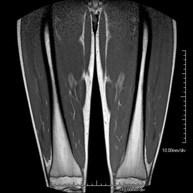

Muscle MRI

This non-invasive diagnostic procedure uses an electromagnetic field and radio waves (from a transmitter and receiver) to acquire high-definition anatomical images of the muscles being examined. It is a radiation-free procedure. Paramagnetic contrast (gadolinium) is used only rarely to improve lesion clarity.